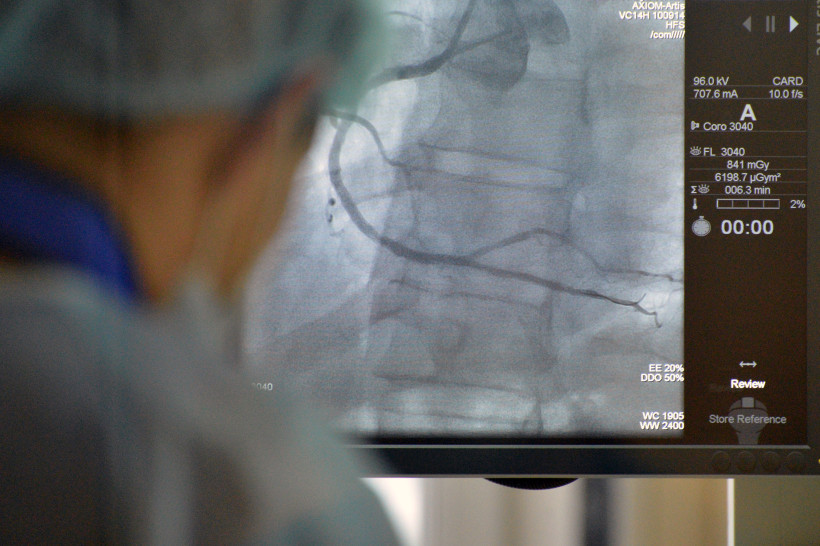

— В результате работы регионального сосудистого центра и первичных отделений смертность населения области при патологии органов кровообращения на данный момент снизилась на 13 %. При этом на 17 % снизилась смертность трудоспособного населения, — отметила Ираида Меньшикова. — В Приамурье значительно выросло число больных, которым оказана высокотехнологичная медицинская помощь (ВМП): с 208 человек в 2010 году до 1 024 в 2015-м. При этом гораздо большее количество ВМП оказывалось в Благовещенске – в клинике кардиохирургии Амурской ГМА и в Амурской областной клинической больнице.

По словам министра здравоохранения Амурской области Николая Тезикова, диагноз «острый инфаркт миокарда» в регионе уже не звучит как приговор. «При этом мы сохраняем не только жизни больным с сердечно-сосудистыми заболеваниями, но и трудоспособность данных пациентов», — отметил министр.